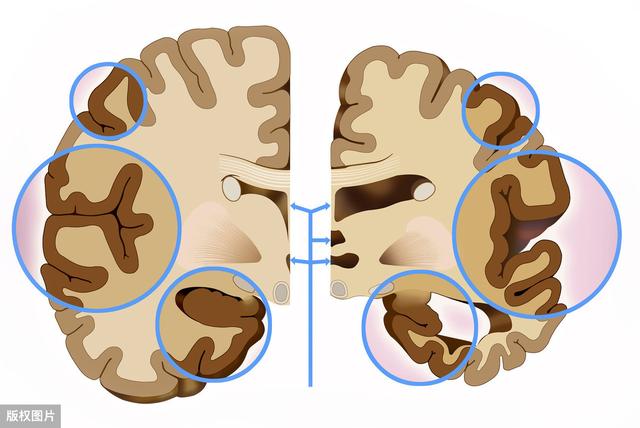

脳萎縮の部位でいえば、大脳萎縮と小脳萎縮に簡単に分類できる。大脳は言語や思考などを司り、小脳は主に平衡感覚を司る。従って、大脳が萎縮すれば、判断力、思考力、言語表現力などにある程度の影響が出ますし、小脳が萎縮すれば、主に運動失調、バランス能力の低下、歩行が不安定になります。大脳萎縮であれ、小脳萎縮であれ、患者に大きな弊害をもたらし、重度の大脳萎縮は認知症にまで発展する可能性がある。

形態学的には、大脳皮質萎縮、小脳萎縮、大脳皮質、小脳および脳幹の萎縮を含むびまん性脳萎縮として現れる。限局性脳萎縮は、外傷、血管疾患、頭蓋内限局性感染症などの限定的な脳の器質的病変の後に最もよくみられる。脳萎縮の最も一般的な原因は、長期にわたる慢性的な脳血液供給不足によるもので、脳細胞が早期に死滅する。

脳は基本的に、原始脳(生命中枢を担当)、感情脳(記憶、感情、言語を担当)、認知脳(認知、論理、思考、計算を担当)の3つの構造に大別できる。脳は身体の体積と重量のわずか2%しかないが、身体のエネルギーの20%を消費する。これは、脳細胞が機能志向の器官であり、常に作動する必要があることを示している。ウォン教授によれば、脳の萎縮という言葉は基本的に2つの観点からアプローチすることができ、私はそれを構造的な区別と機能的な区別に分類している。